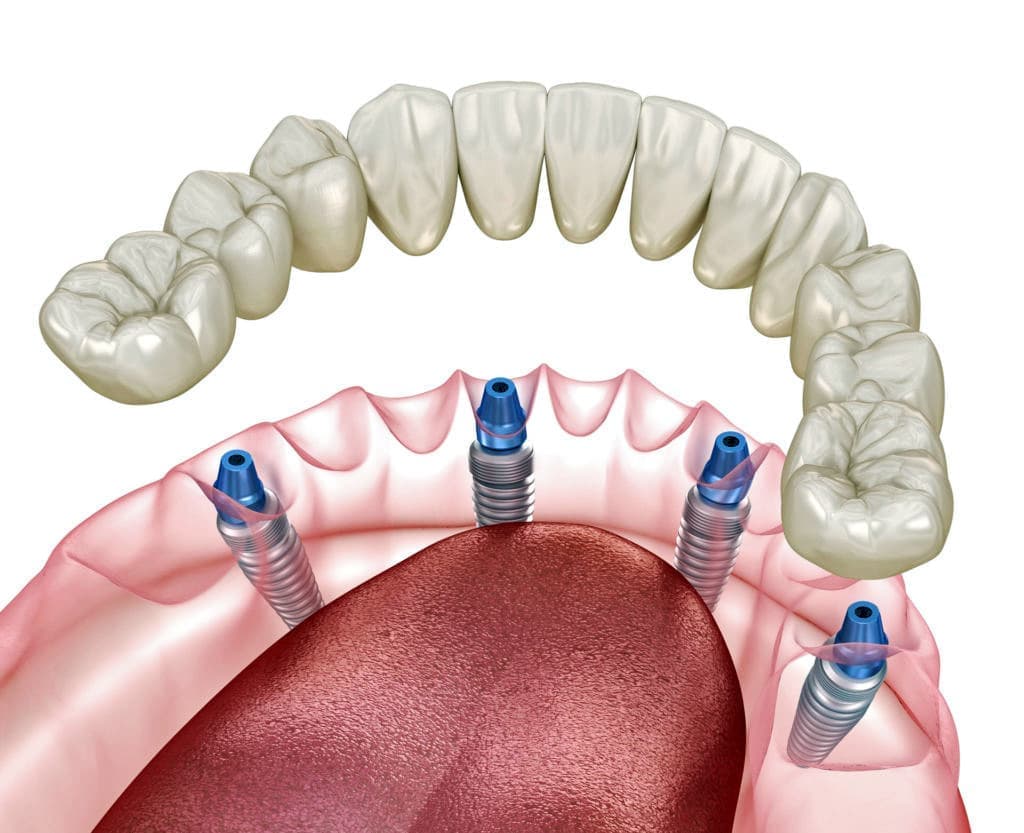

現代歯科医学の中で、失った歯を再現し、咬合を回復するにはインプラントが最良の治療法と考えられております。

天然歯のような見栄えだけでなく、これまでの入れ歯やブリッジでは満足することが難しかった「食べる・話す」という機能も回復できます。